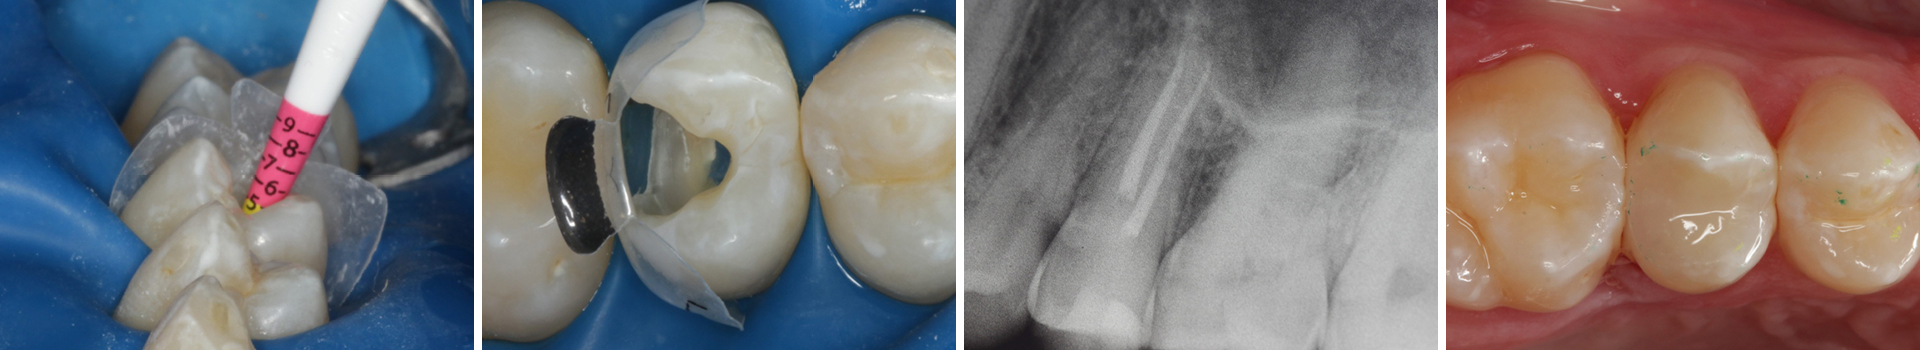

Abbildung 1

Bissflügelröntgenaufnahme, Approximalraumkaries an Zahn 25 distal

Abbildung 2

Intakte Kaufläche

Folgesitzung: Trepanation Zahn 25

Abbildung 25

Nadelaufnahme nach elektronischer Längenmessung

Abbildung 26

Wurzelkanäle gefüllt

Abbildung 27

Kontrollröntgenaufnahme

Abbildung 28

Kompositrestauration nach „Schachtverschluß“; keine Krone geplant